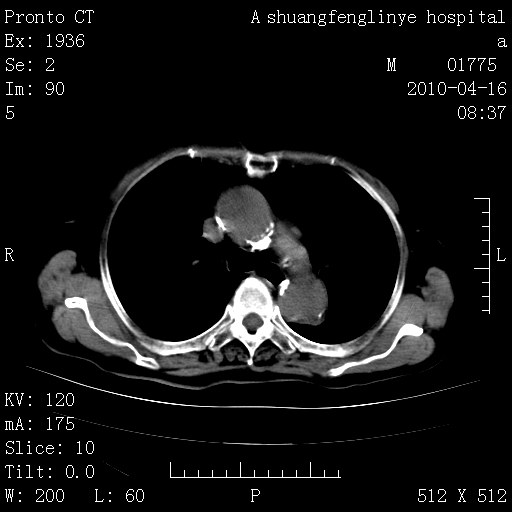

标题: CT25784:咳痰、请会诊!结核? [打印本页]

标题: CT25784:咳痰、请会诊!结核?

陈旧性结核,胃腔扩大,脾脏受压后移

慢支肺气肿,左上陈旧性结核,主动脉冠脉钙化

典型 夹层动脉瘤。 内膜瓣钙化移位

1)左肺上叶结核(纤维、增殖病灶)。2)冠状动脉及主动脉钙化。

1)左肺上叶结核(纤维、增殖病灶)。2)冠状动脉及主动脉钙化。肺动脉高压